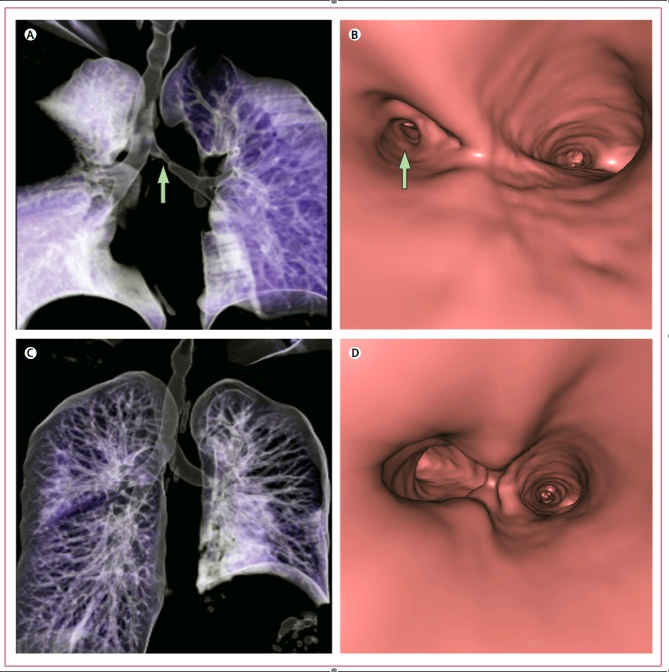

Figure 1: Volume-rendering CT of the bronchoscopic reconstruction before (A&B) and after (C&D) engraftment.

Results and Discussion: 10 days later the patient left the hospital and post-surgical bronchoscopy revealed that there were no complications and that the patient’s lung function had returned to normal. After four days it was noted that the graft was almost indistinguishable. The patient has since been able to go on walks and lead a more normal life.